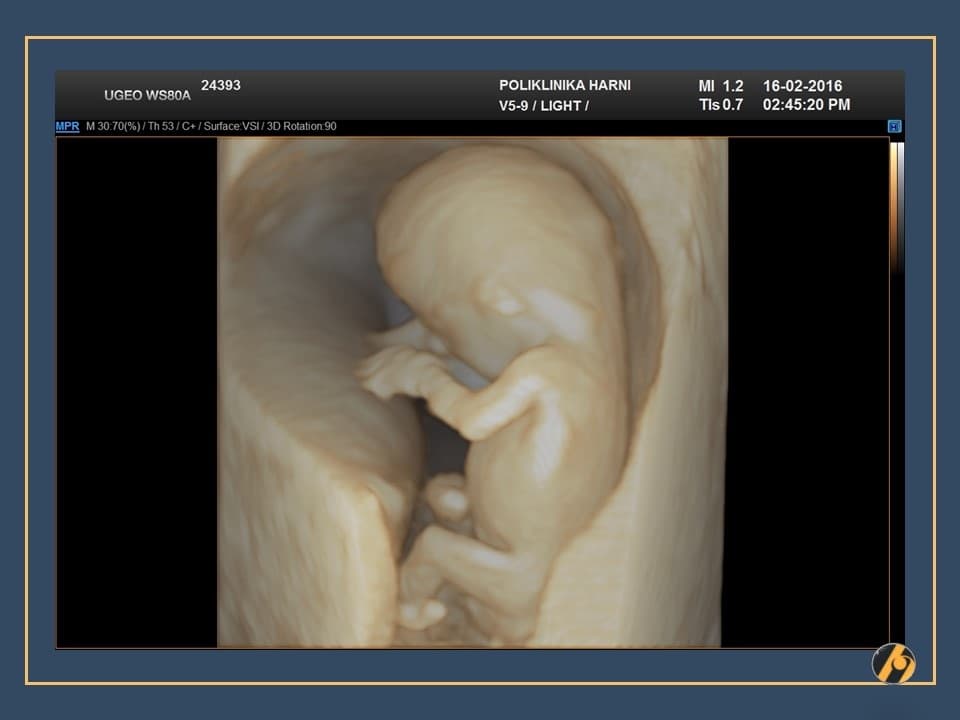

Konačno je dovršen veliki posao, završena je embriogeneza i vaša beba je kompletno razvijena. Od sada pa do konca trudnoće najveće promjene se odnose na dobitak na težini i rast bebe. Beba se od sada više ne naziva embrij, nego fetus.

Premda je dovršena embriogeneza, organogeneza i fetalni rast se nastavljaju ubrzanim tempom, pa je beba u zadnja dva tjedna udvostručila svoju težinu.

Nastavlja se oblikovanje lica koje je sve više nalik ljudskom licu. Razvitkom noktiju na rukama i nogama završava se razvitak prstića. Beba je veoma pokretna i kod ultrazvučnog pregleda se zapažaju nagli i snažni pokreti tipa trzaja - pokreti su spontanog karaktera, ali bez volje djeteta. U ovo vrijeme je kontrola pokreta djeteta još uvijek podređena živčanim središtima u leđnoj moždini, a moždani centri za koordinaciju pokreta još nisu razvijeni.

U ovome tjednu se crijeva u potpunosti smještaju u trbušnu šupljinu i ukoliko se prije vidjela omphalocoela (prisustvo crijeva u pupčanoj vrpci), sada se ta slika gubi. Formirano je i raspoznatljivo vanjsko spolovilo, koje se standardnim ultrazvučnim tehnikama još neko vrijeme neće moći raspoznati.

Vaša beba dugačka je oko 6.5 cm, a teška 10 - 15 g.